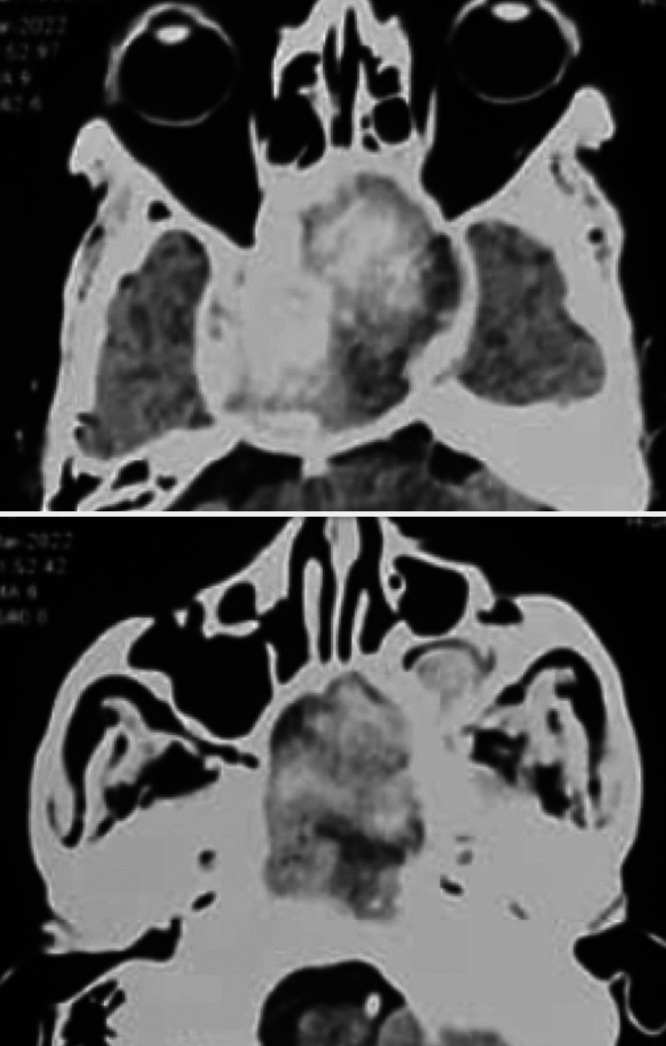

FIG. 4.

CT angiography of head and neck vessels showing 60 × 60 × 72–mm thrombosed right CCA aneurysm (upper) with extension into the nasal cavity and left maxillary sinus (lower).